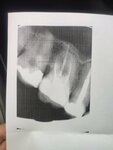

2 балла за некачественно оказанную услугу. Вот такой снимок мне дали. Не дорого, всего 180 рублей но, деньги заплачены, снято с промахом (светили зуб что справа), снимок отвратительный и не информативный. Персонал показался приветливым и добродушным. После консультации там лечить зубы в дальнейшем не планирую.